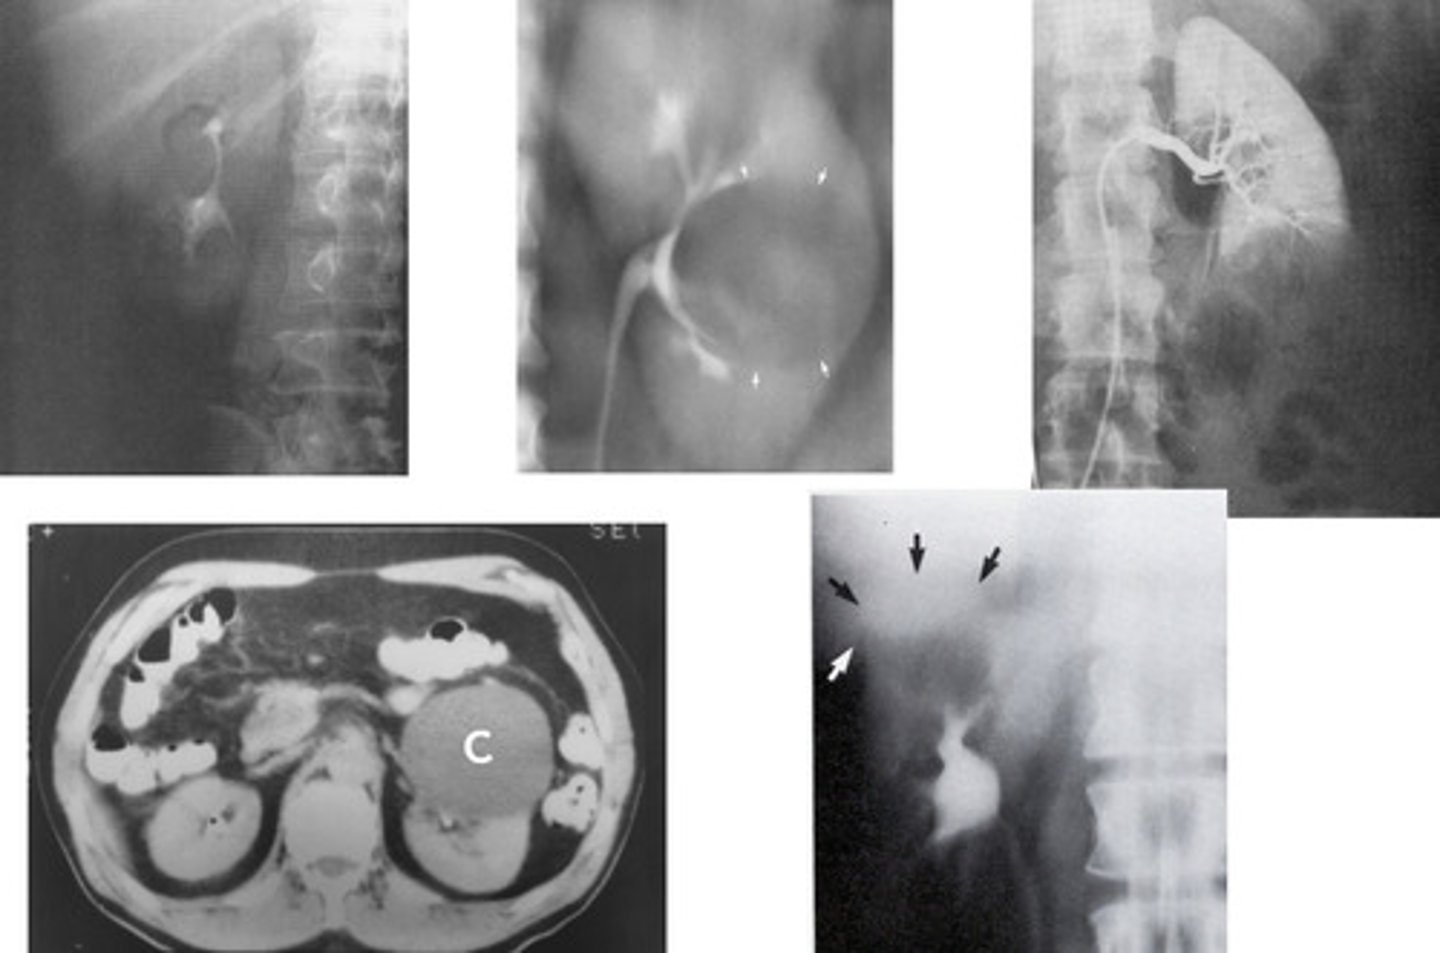

- Wilms Tumor / Nephroblastoma

- Infants and children

- What type of renal neoplasm arises from the embryonic renal tissue that distorts the calyces and creates a vine like blood supply?

- This is the most common abdominal neoplasm in who?

- Neuroblastoma

- second / children

- What type of abdominal neoplasm arises from the adrenal gland (endocrine system) and pushes down on the kidney?

- This is the _________ most common abdominal neoplasm in whom?

- Renal Cell Carcinoma

- Over 40 years

- Hematuria

- It's malignant (90% chance)

- Calyces and walls

- CT and MRI